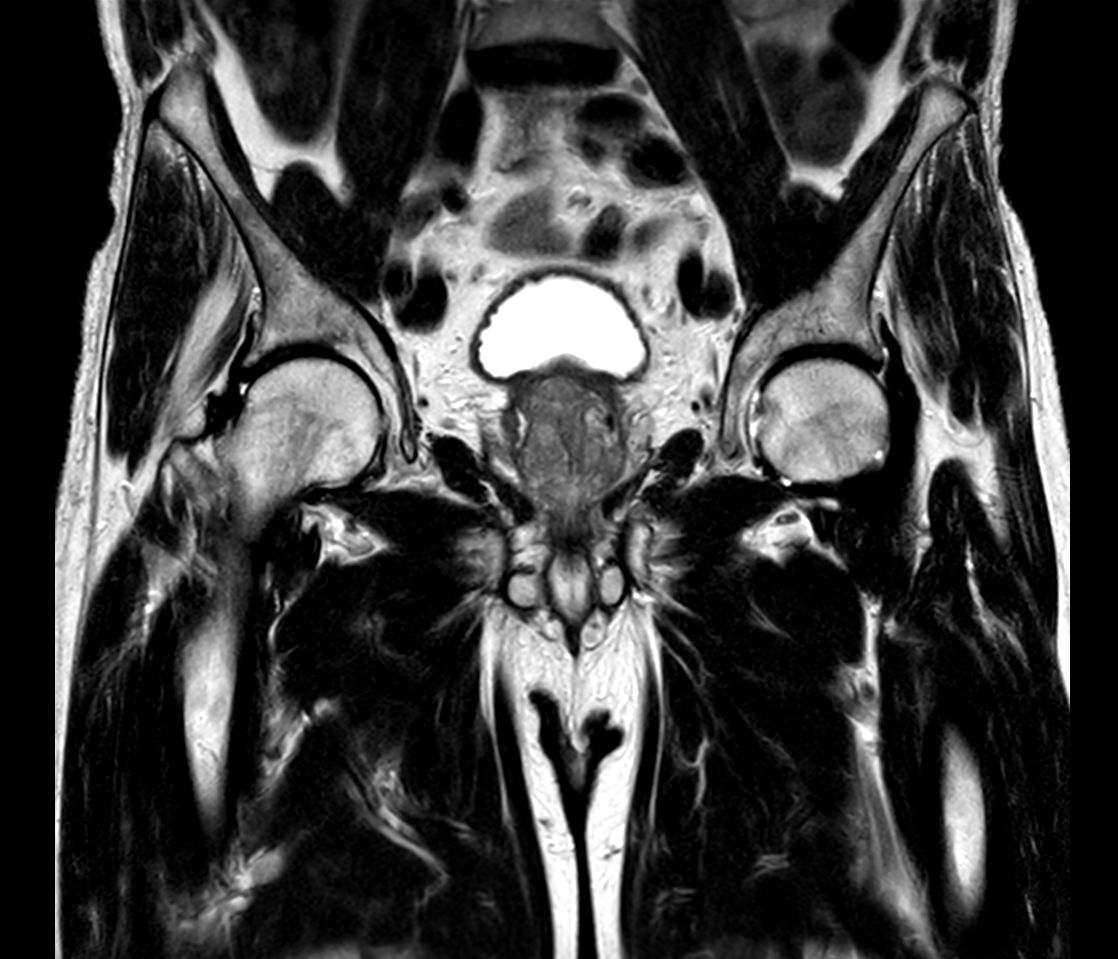

Patient with a penile carcinoma. ExamCard includes Compressed SENSE to shorten exam time, diffusion to achieve high contrast between background and lesions, and MultiVane XD for motion-free imaging in short scan time.

T1w TSE Compressed SENSE